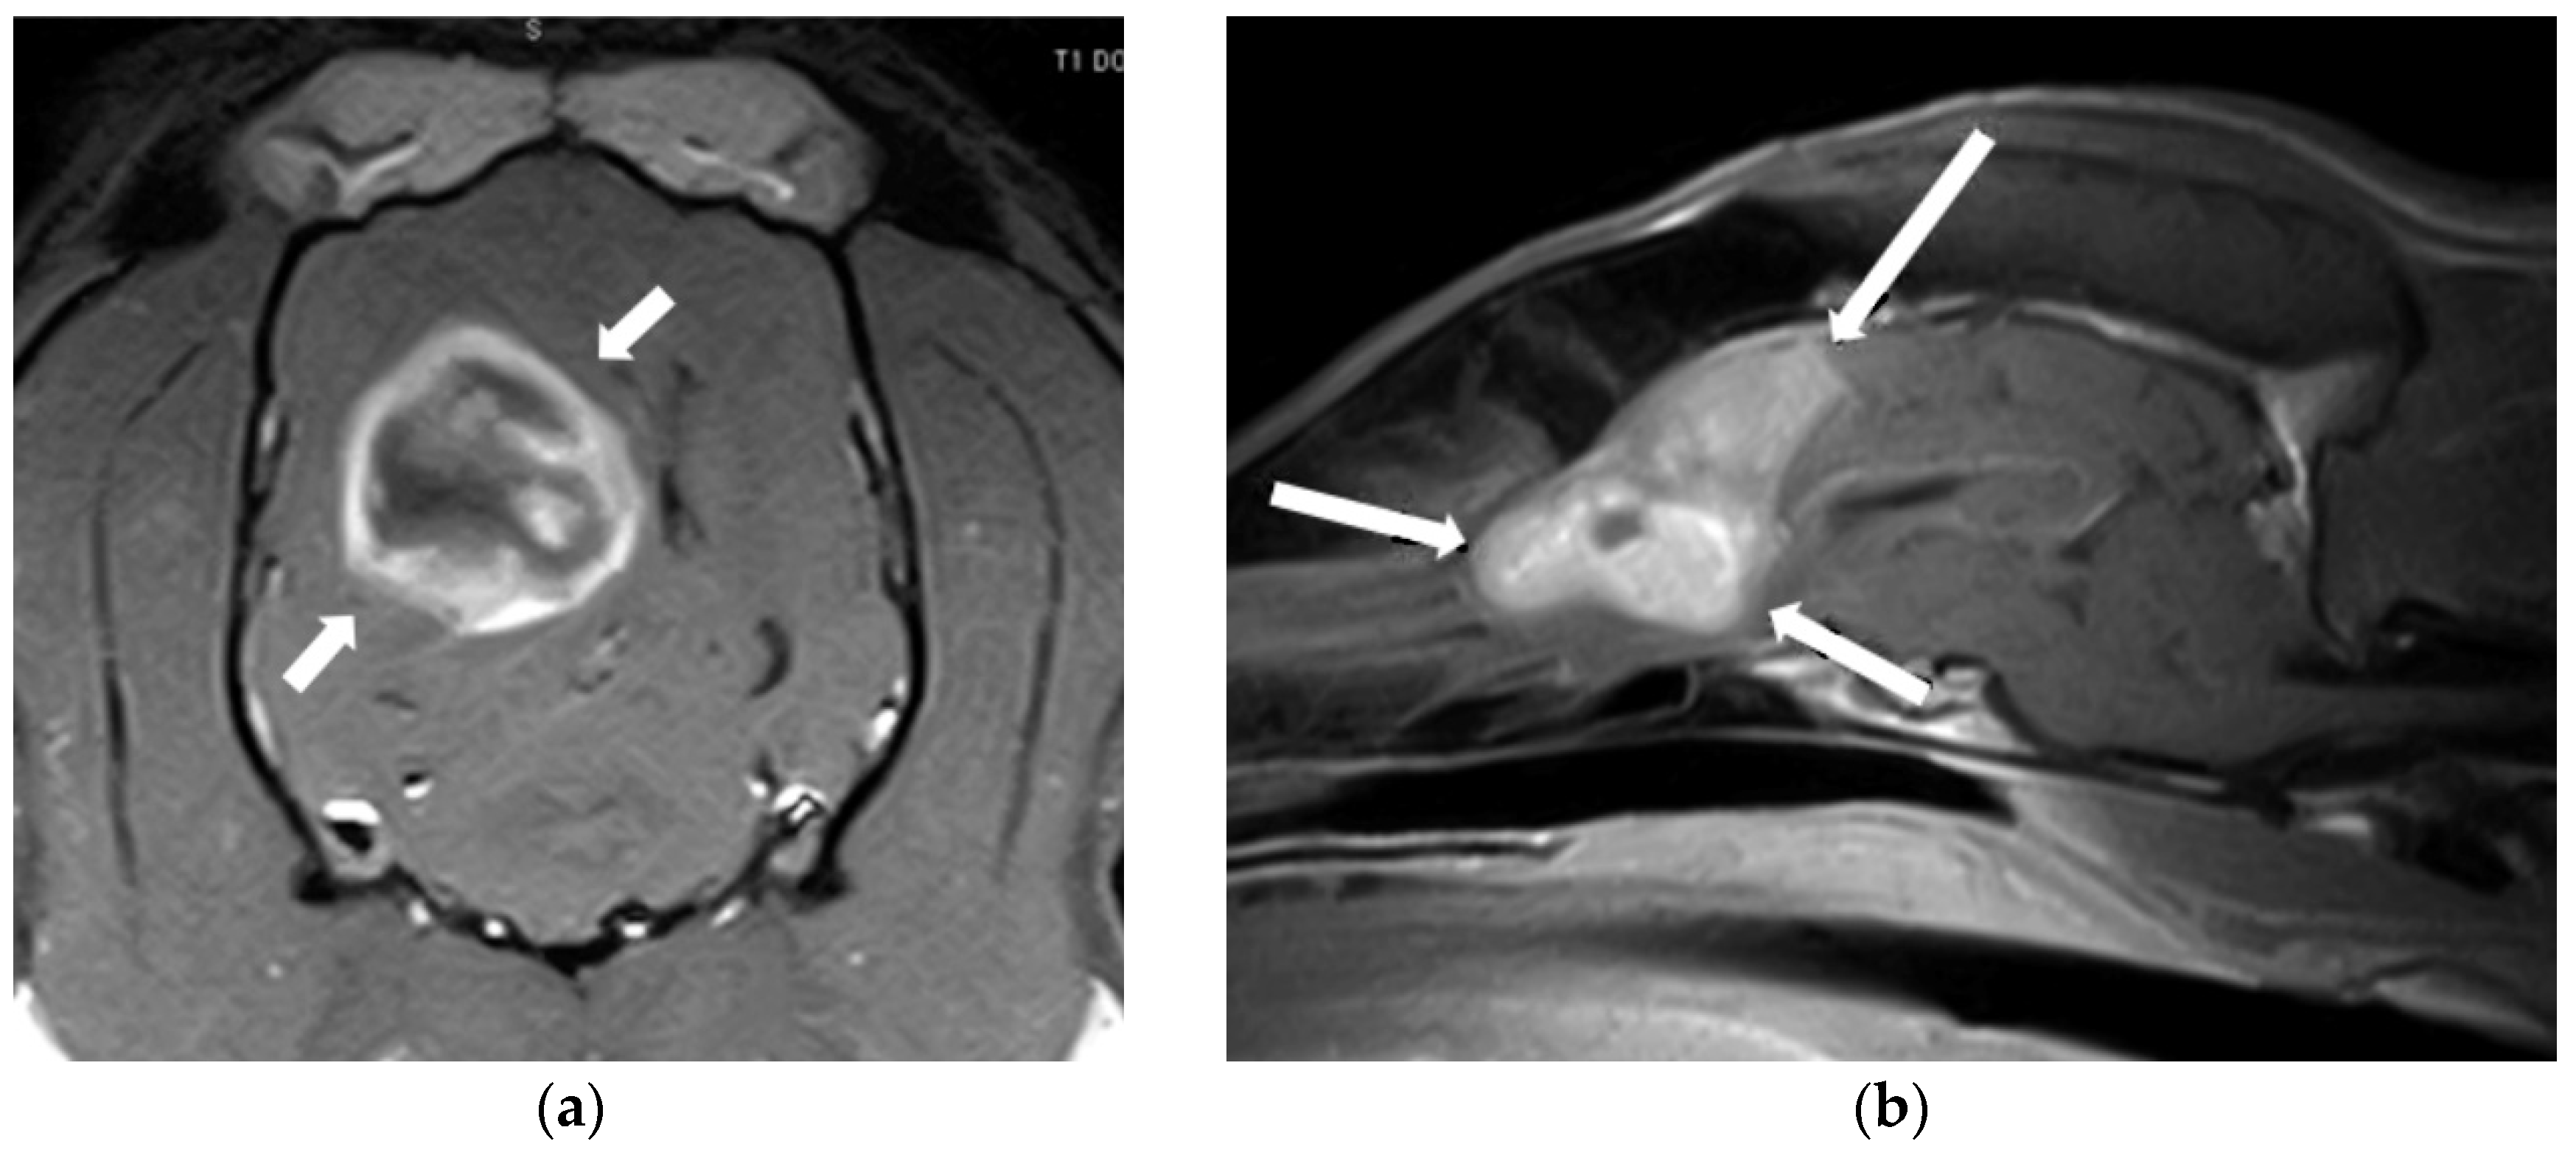

2.1. Intracranial Neoplasia

- Stadler, K.L.; Ruth, J.D.; Pancotto, T.E.; Werre, S.R.; Rossmeisl, J.H. Computed Tomography and Magnetic Resonance Imaging Are Equivalent in Mensuration and Similarly Inaccurate in Grade and Type Predictability of Canine Intracranial Gliomas. Front. Vet. Sci. 2017, 4, 157. [Google Scholar] [CrossRef]

- Cherubini, G.B.; Mantis, P.; Martinez, T.A.; Lamb, C.R.; Cappello, R. Utility of Magnetic Resonance Imaging for Distinguishing Neoplastic from Non-Neoplastic Brain Lesions in Dogs and Cats. Vet. Radiol. Ultrasound 2005, 46, 384–387. [Google Scholar] [CrossRef]

- Wolff, C.A.; Holmes, S.P.; Young, B.D.; Chen, A.V.; Kent, M.; Platt, S.R.; Savage, M.Y.; Schatzberg, S.J.; Fosgate, G.T.; Levine, J.M. Magnetic Resonance Imaging for the Differentiation of Neoplastic, Inflammatory, and Cerebrovascular Brain Disease in Dogs. J. Vet. Intern. Med. 2012, 26, 589–597. [Google Scholar] [CrossRef]

- Wisner, E.R.; Dickinson, P.J.; Higgins, R.J. Magnetic Resonance Imaging Features of Canine Intracranial Neoplasia. Vet. Radiol. Ultrasound 2011, 52, S52–S61. [Google Scholar] [CrossRef]

- Bentley, R.T. Magnetic Resonance Imaging Diagnosis of Brain Tumors in Dogs. Vet. J. 2015, 205, 204–216. [Google Scholar] [CrossRef]